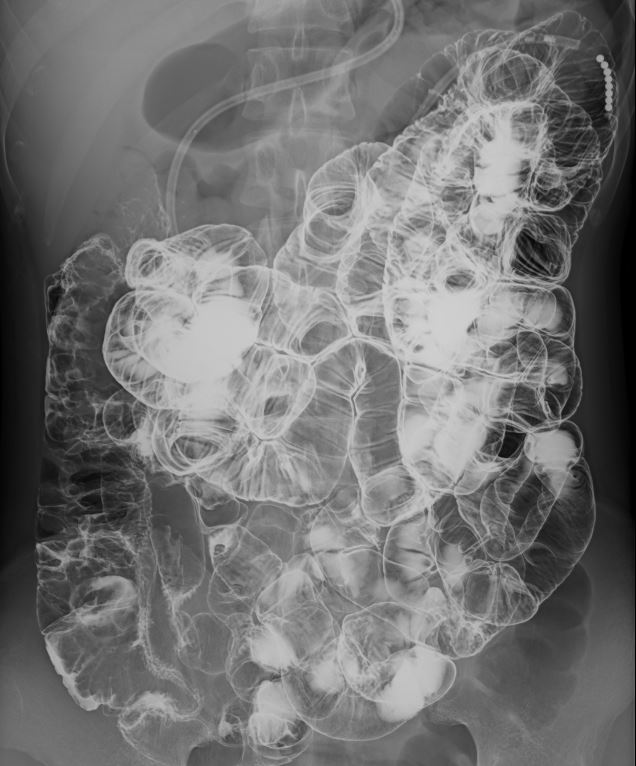

大腸造影検査は、造影剤を使って大腸の内部をX線で映し出し、ポリープや腫瘍、炎症などの異常を調べることができます。腸が重なり病変がわかりにくい場合は複数の角度からX線撮影し、それらの画像をコンピューターで立体的に再構成する断層撮影を行います。これにより、通常の撮影では見えにくい腸の重なりを分離して、より詳細で正確な画像が得られます。

大腸造影 |

大腸の断層画像 |